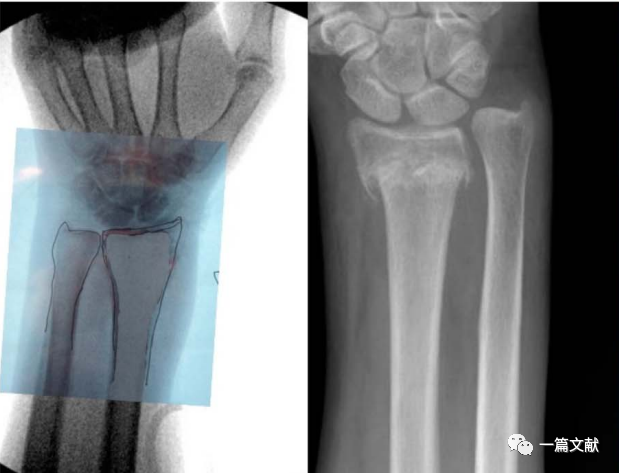

腕关节手术

虽然一般认为,术中恢复桡骨远端23°尺偏角,11°掌倾角,13mm的桡骨高度,即获得了良好的骨折复位。但是存在个体差异,例如尺骨变异患者。故此时,将患者健侧肢体作为参考对象最可靠。如下图:

左侧为健侧临摹图,右侧为骨折图

将此临摹图翻转后作为基准,进行骨折复位与固定